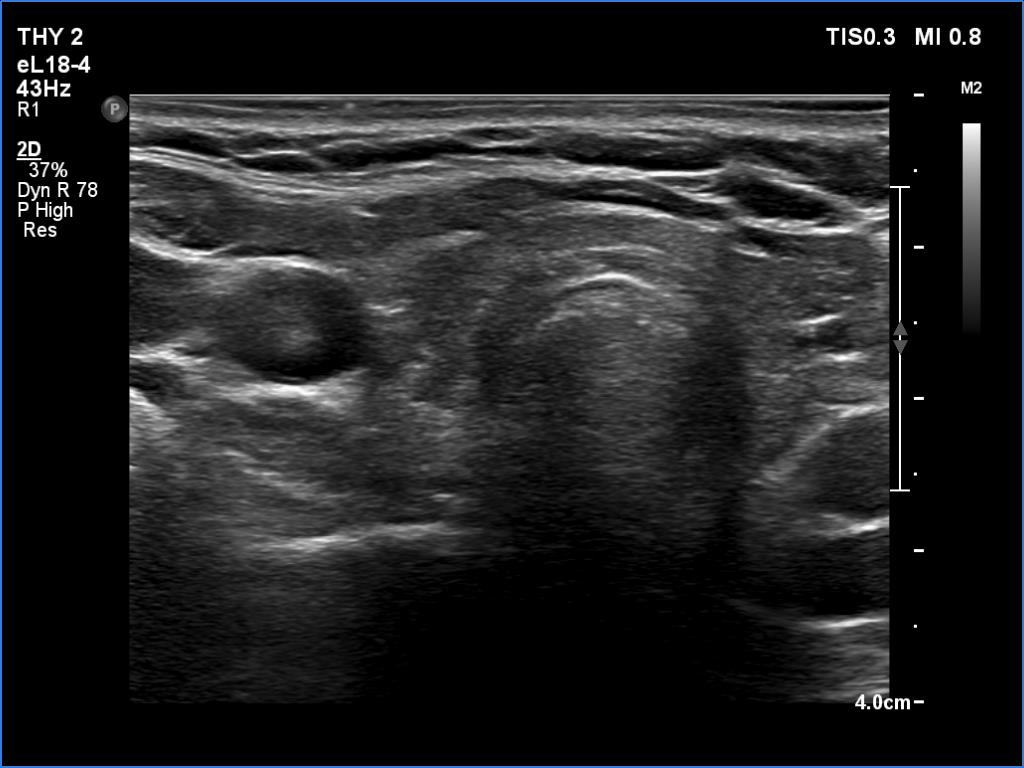

First examination (1st to 3rd rows of images):

Clinical presentation: A 29-year-old woman was referred for an evaluation of neck complaints. She has noticed tenderness in the left side of the neck 3 weeks. One week prior to the examination, pain appeared in the right thyroid. Her body temperature was normal as was the erythrocyte sedimentation rate and CRP, 14 mm/H and 4.1 mg/L (normal value 0-4.8), respectively.

Palpation: The right lobe was tender while the left was painful and hard.

Functional state: subclinical hyperthyroidism with TSH 0.01 mIU/L and FT4 19.1 pM/L, aTPO 2 U/mL.

Ultrasonography: The thyroid was echonormal. There were multiple hypoechogenic areas with ill-defined borders in both lobes. According to the hypoechogenic areas, the vascularization was practically absent.

Aspiration cytology was performed from the painful right lobe and resulted in subacute, granulomatous, de Quervain's thyroiditis.